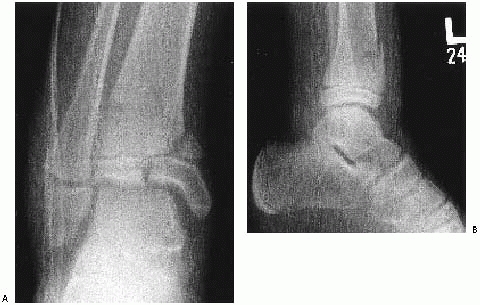

![]() |

FIGURE 26-16 Triplane with deltoid injury and syndesmosis widening with stress views. A,B. Injury films. C-E. Postoperative films.

mortise view of the ankle is essential in addition to anteroposterior

the distal fibula. The vertical component of a triplane or Tillaux

fracture can be hidden behind the overlying fibular cortical shadow.107 A study by Vangsness and coworkers186